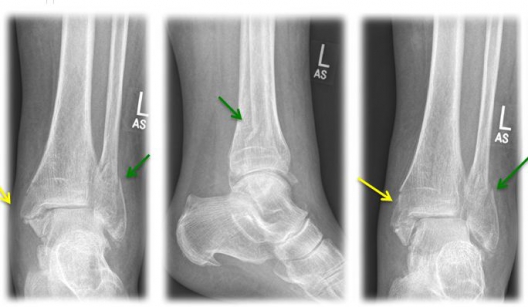

undefined

Fig. 3) "Bimalleolar ankle joint fracture" left x-rayed in 3 planes (a.p., lateral, internal rotation) with an internal ankle fracture (yellow arrow) and a spiral external ankle fracture (green arrow)